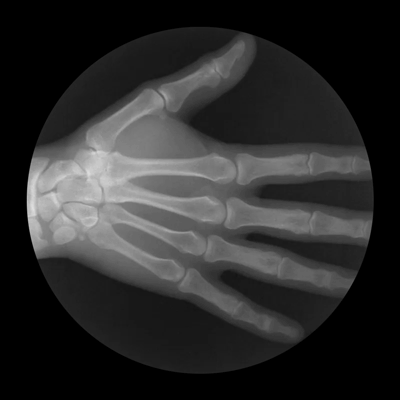

Кисть состоит из запястья, пясти и фаланг пальцев. Запястье образовано двумя рядами костей: проксимальный ряд содержит ладьевидную, полулунную, трехгранную и гороховидную кости, а дистальный ряд — кость-трапецию, трапециевидную, головчатую и крючковидную кости. Дистальнее запястья лежат пять пястных костей, а за ними — фаланги пальцев, причем у большого пальца их две (проксимальная и дистальная), а у остальных пальцев — три (проксимальная, средняя и дистальная).

Биомеханика пястно-фаланговых суставов на рентгене

Дистальный конец лучевой кости с одной стороны и ладьевидная, полулунная и трехгранная кости запястья с другой образуют лучезапястный сустав. В нем возможны сгибание, разгибание, отведение (отклонение кисти в сторону лучевой кости) и приведение (отклонение кисти в сторону локтевой кости) (рис. 7.1). Дистальный ряд костей запястья и пястные кости образуют запястно-пястные суставы. Дистальные концы пястных костей и проксимальные фаланги пальцев формируют пястно-фаланговые суставы, в которых также возможны сгибание, разгибание, отведение и приведение. На всех пальцах, кроме большого, есть два межфаланговых сустава: проксимальный и дистальный; в них возможны только сгибание и разгибание. Суставы кисти укреплены суставными капсулами и многочисленными связками.